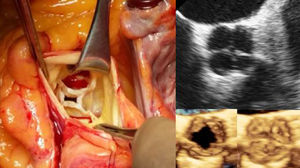

En estas imágenes se aprecia la evaluación quirúrgica de la válvula aórtica donde se objetivaron 4 velos, 2 de ellos del mismo tamaño, el coronariano izquierdo (VCI) y el no coronariano (VNC), y otros 2 velos diferentes, el coronariano derecho (VCD) y el velo accesorio, y las imágenes ecocardiográficas correspondientes, en 2D y su reconstrucción en 3D.

El caso que nos ocupa es un varón de 70 años que consulta por disnea. El ETT mostró una VAQ con reducción de la movilidad de los velos y una insuficiencia aórtica severa. Se realizó un cateterismo prequirúrgico que descartó cualquier anomalía coronaria. En la evaluación quirúrgica de la válvula se objetivaron 4 velos, 2 de ellos del mismo tamaño, coronariano izquierdo (VCI) y no coronariano (VNC), y otros 2 velos diferentes, coronariano derecho (VCD) y velo accesorio, correspondiéndose con el tipo F, de acuerdo a la clasificación de Hurwitz y Roberts (fig. 1). El anillo aórtico en la zona de la neo-cúspide (entre el VCD y VNC) se encontraba normoposicionado, factor a tener en cuenta para evitar la posible afectación del tejido de conducción. Se procedió a la sustitución de la válvula aórtica por una prótesis biológica Edwards CEP Magna® de 21mm. El paciente fue dado de alta al 6.° día del postoperatorio sin complicaciones durante su estancia. Actualmente se encuentra en clase funcional de la NYHA I.